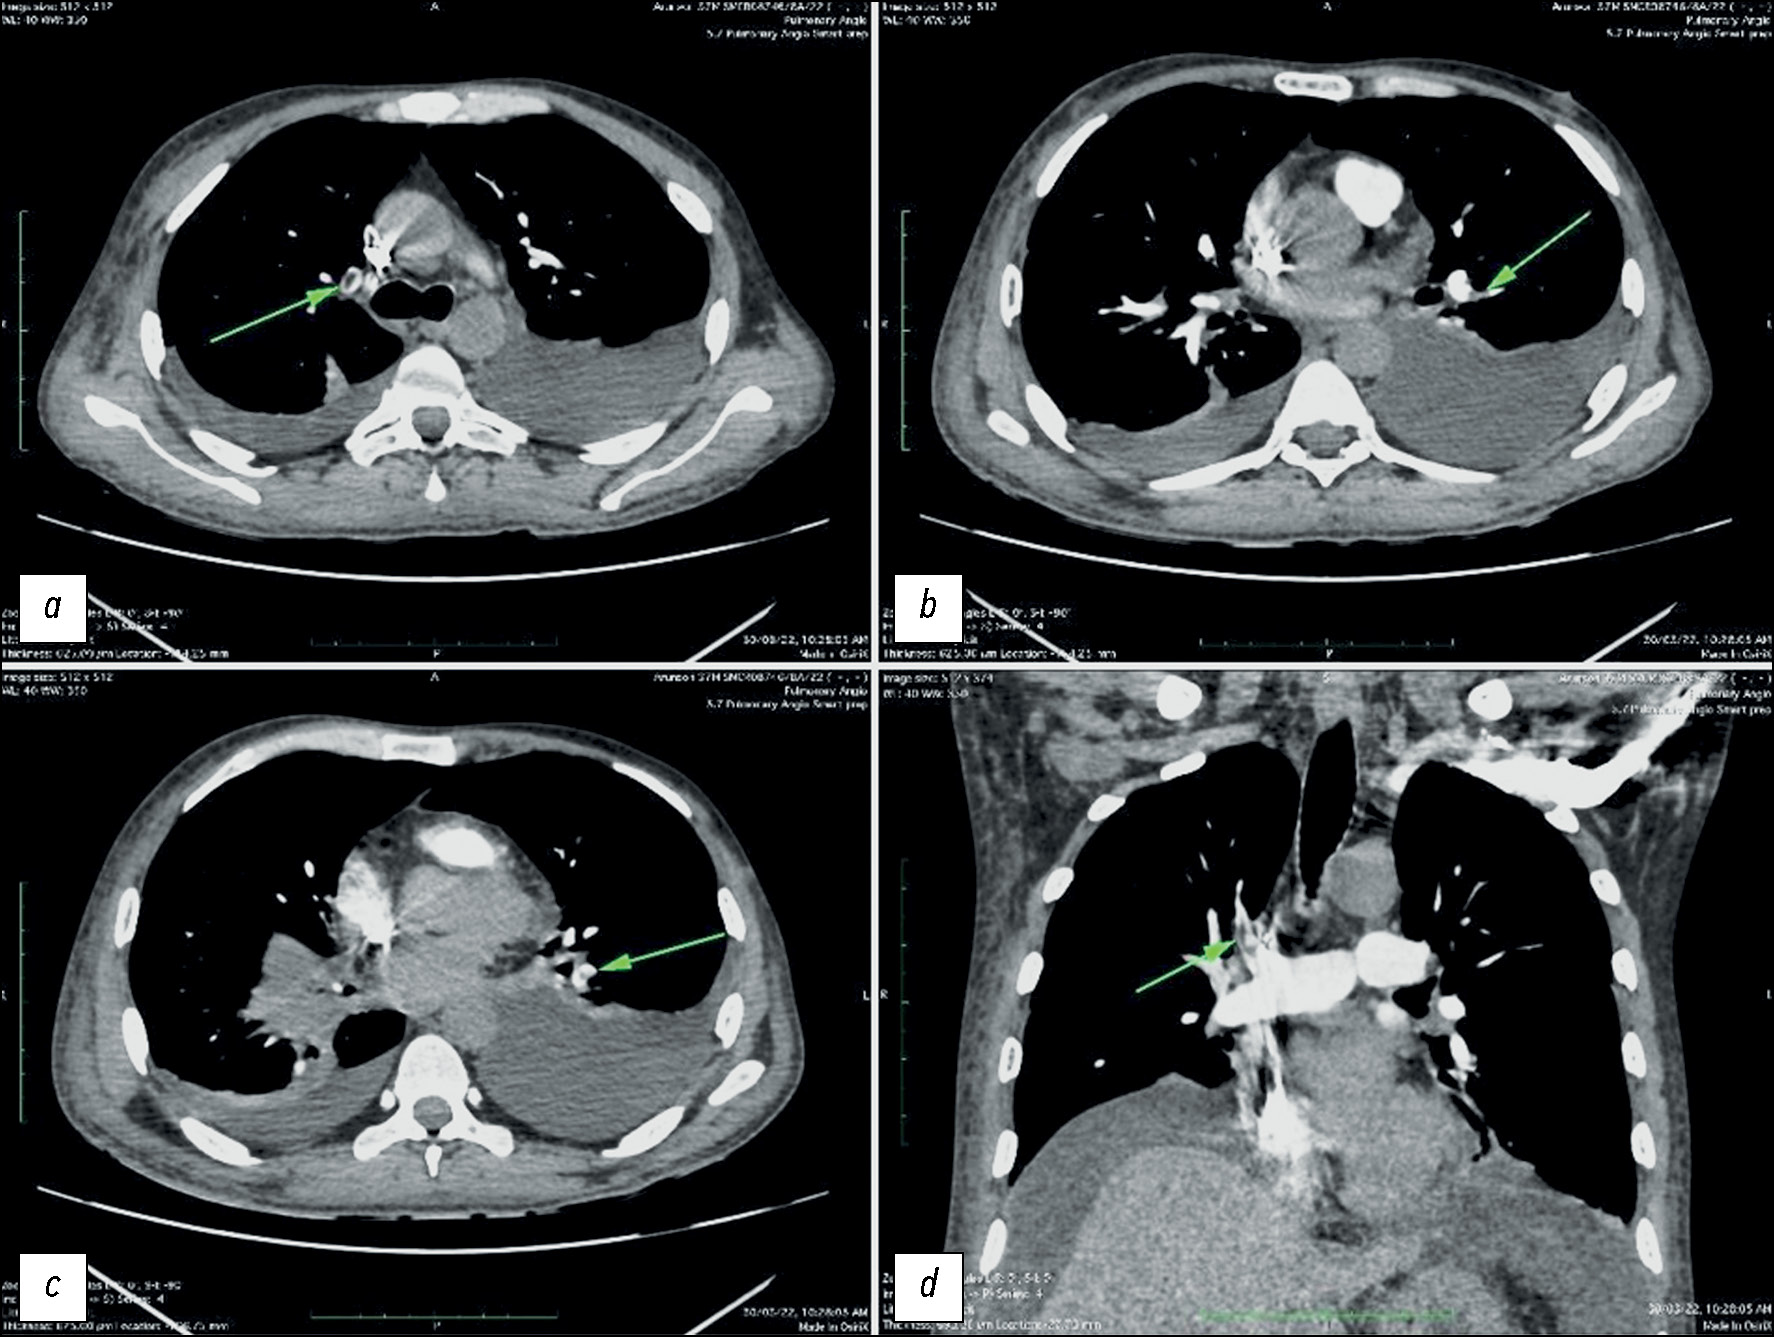

Pulmonary artery pseudoaneurysm in a young man with pulmonary hypertension on computed tomography angiography

Abstract

Pulmonary artery aneurysms and pseudoaneurysms are uncommon anomalies; however, their associated morbidity underscores the importance of recognizing them. Herein, we present a clinical case involving a 15-year-old male patient who presented at our clinic with complaints of hemoptysis. Upon diagnosis, a left lung aneurysm was found. Subsequent computed tomography angiography and intervention on the pulmonary arteries confirmed the presence of pulmonary artery aneurysms, elucidating that the hemoptysis was caused by the rupture of the aneurysm. The intervention on the pulmonary artery further confirmed the diagnosis. Early detection and management of pulmonary artery aneurysms are crucial, particularly in young patients, as timely intervention can prevent severe complications and improve patient outcomes. Raising awareness of these vascular abnormalities and promptly addressing them through appropriate diagnostic measures and interventions can help healthcare providers effectively mitigate the potential risks associated with pulmonary artery aneurysms, thereby enhancing patient care and prognosis.